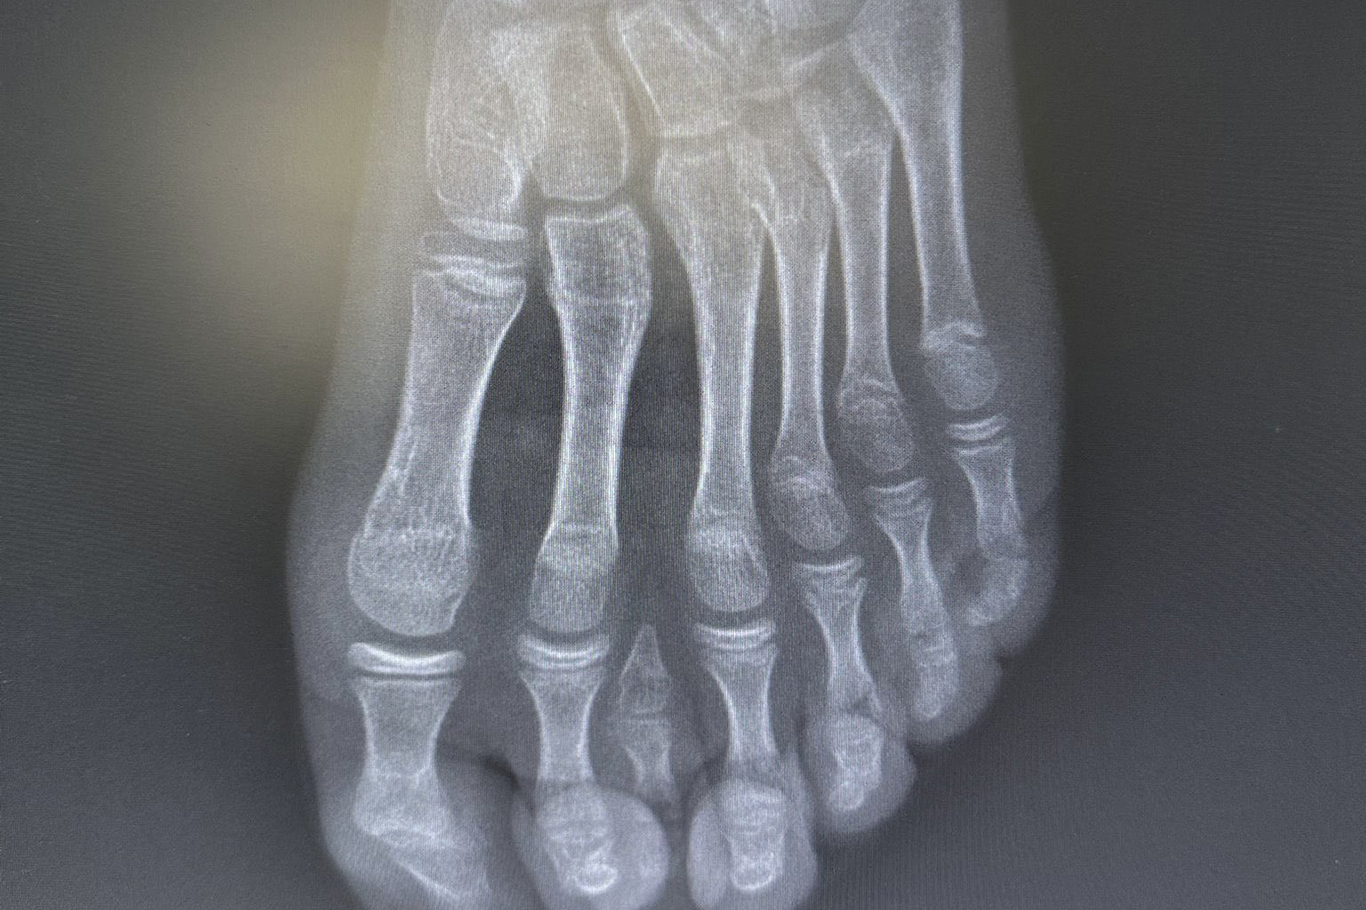

Batman Eğitim ve Araştırma Hastanesi’nde tedavi edilen E.H., doğumsal olarak 7 parmaklı ayak (polidaktili) tespit edildi.

Yetkililer, el ve ayaklarda fazla ya da eksik parmak vakalarına zaman zaman rastlandığını ancak 7 parmaklı ayak olgularının oldukça nadir görüldüğünü belirtti.

Uzmanlar, mevcut altı parmağa müdahale edilmesinin ayak biyomekaniğini ve dengesini olumsuz etkileyebileceğini değerlendirdi.

Bu doğrultuda cerrahi planlama yeniden yapılarak, fonksiyonel açıdan yetersiz ve estetik olarak problem oluşturan tek parmağın çıkarılmasına karar verildi. Operasyon sırasında diğer parmaklara ait damar ve sinir yapıları titizlikle korunurken, mikrocerrahi teknikler kullanılarak işlem sorunsuz şekilde tamamlandı.